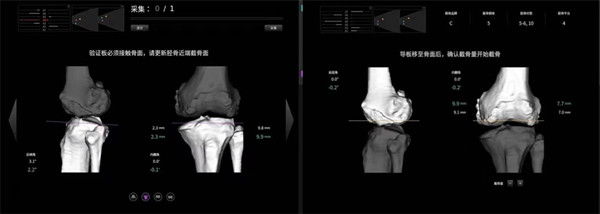

该手术使用的“ARTHROBOT”七轴髋膝兼容关节手术机器人,在术中可对膝关节活动度、下肢对线与关节间隙进行实时评估,依照术中实际情况实时调整规划方案,并按规划精准完成股骨与胫骨侧的截骨,误差控制在1mm与1˚范围以内,实现膝关节个性化、精准化手术治疗。